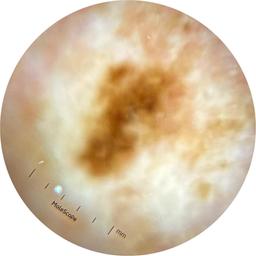

ISIC_5202282

acquisition_day 48

age_approx 50

anatom_site_1 Upper extremity

anatom_site_general upper extremity

diagnosis_1 Benign

diagnosis_confirm_type single image expert consensus

family_hx_mm True

fitzpatrick_skin_type I

image_manipulation instrument only

image_type dermoscopic

personal_hx_mm True

sex female